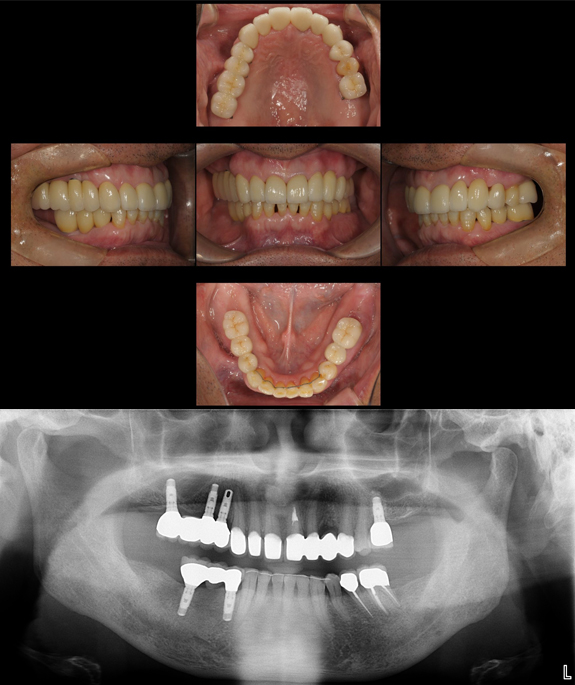

症例3

術前

上下の前歯と奥歯がすれ違っていて最も機能回復が難しいケースです。

術後

インプラントを用いて、しっかりとした噛み合わせを作りしました。